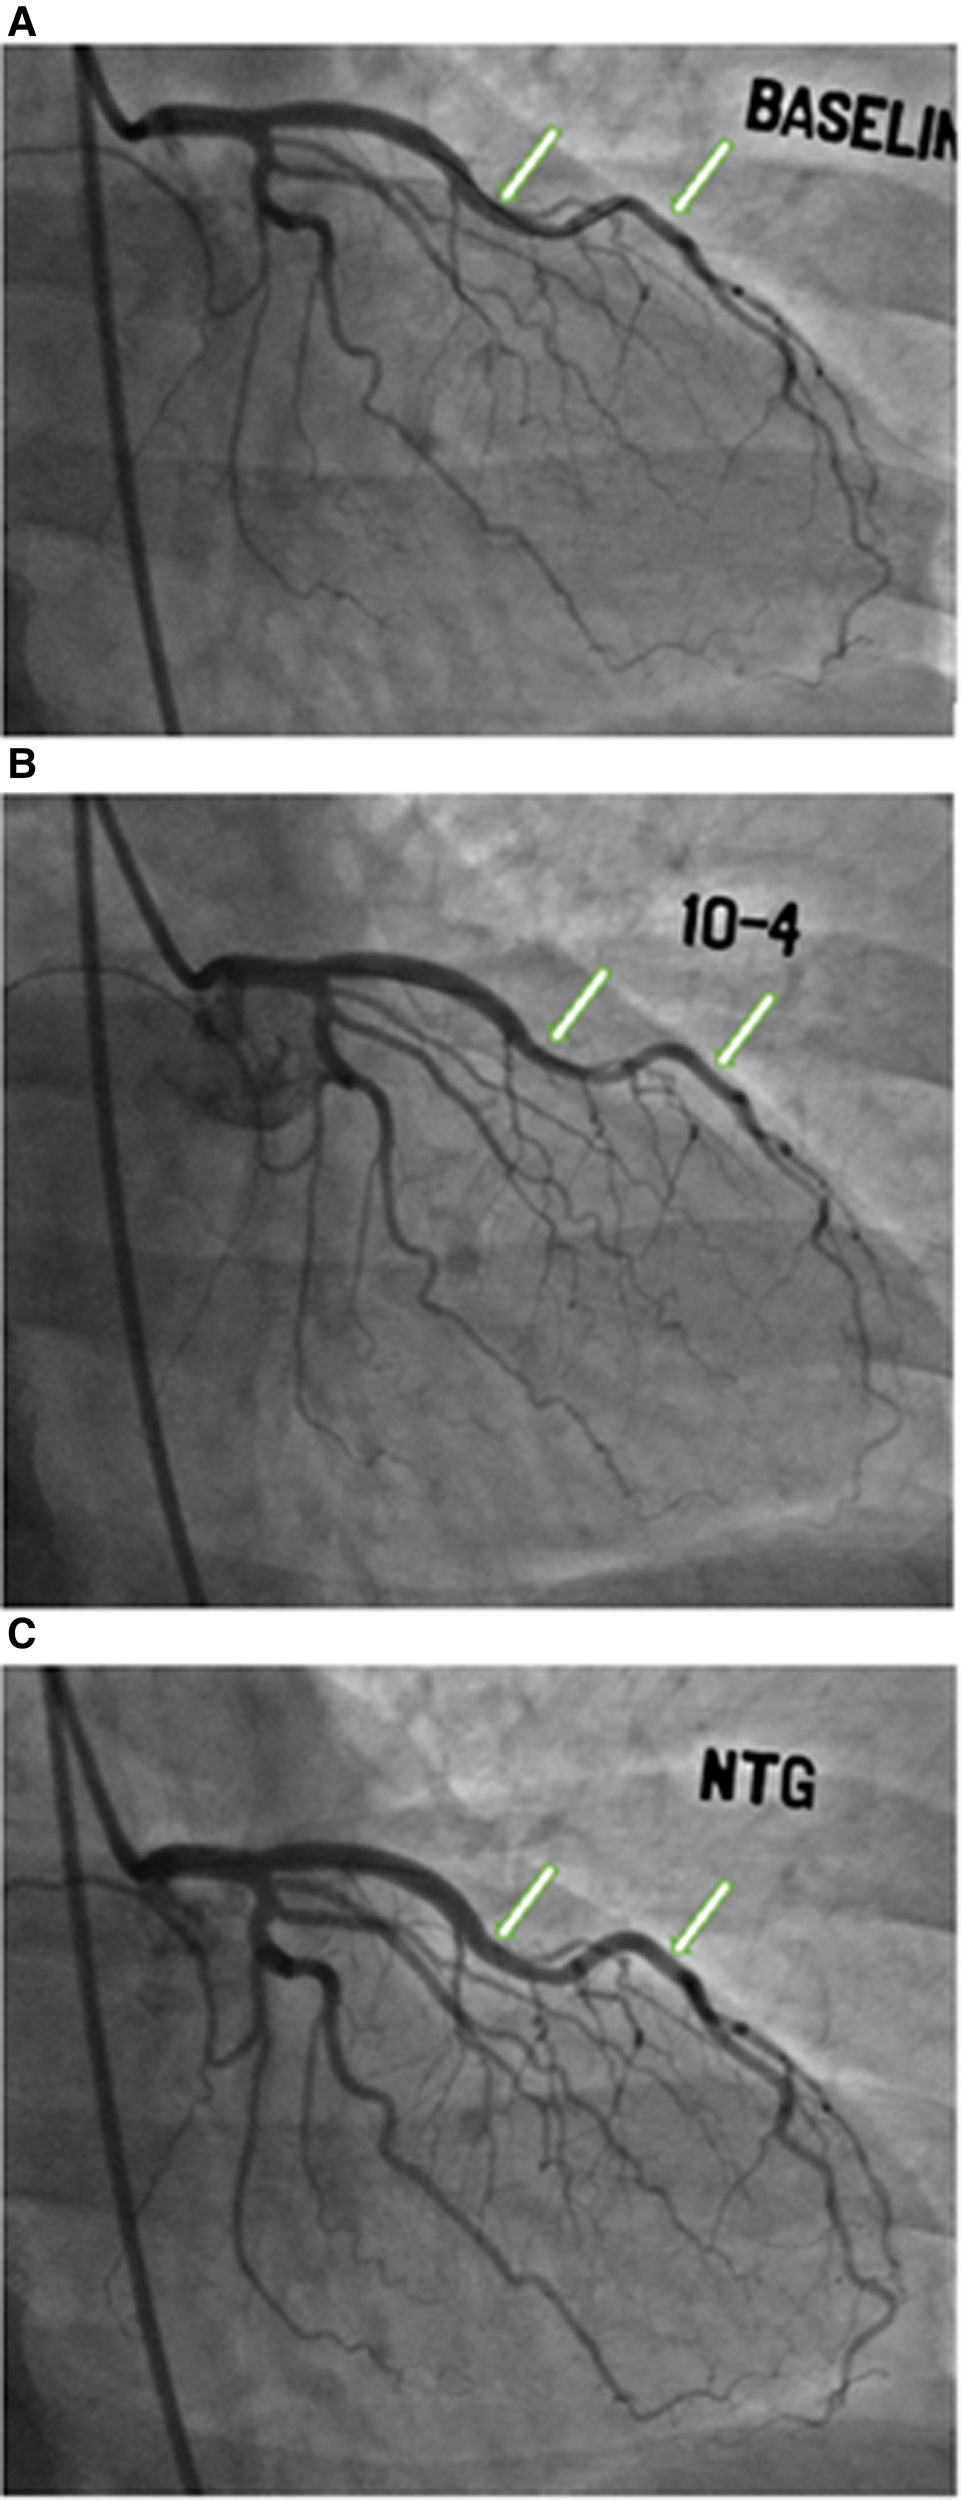

The study design is summarized in Figure 1. Of the 437 women enrolled in the WISE-CVD cohort, 400 answered the ARD question, 240 underwent clinically indicated invasive coronary function testing, and 207 had at least one abnormal invasive coronary function variable indicating CMD. Of the 207 patients with CMD detected on invasive coronary function testing, 19 (9%) had a confirmed history of ARD, and 183/207 (88%) completed the baseline CMR. Figure 2 illustrates a representative abnormal coronary function testing result of a participant with ARD.

Figure 2

Coronary function testing of a participant with ankylosing spondylitis. Arrows show abnormal vasoconstriction of left anterior descending artery after acetylcholine administration (B) compared to baseline (A), with vasodilation after nitroglycerin administration (C)